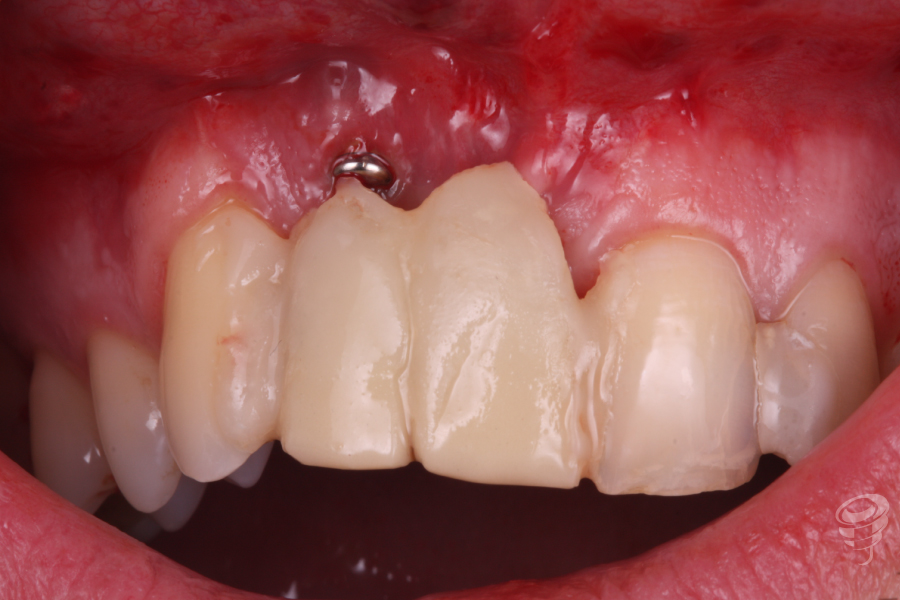

En este caso clínico el paciente presenta un implante colocado en una posición errónea en el sector anterior.

Acude a consulta demandando una solución para un implante situado en posición 12. Este implante nunca se ha rehabilitado debido a su mala situación clínica y radiográfica.

Imagen 1